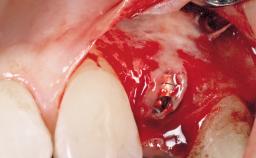

A 30-year-old female patient had lost tooth 21 and was referred to our clinic for consultation and treatment. Due to advanced apical infection, tooth 21 had been extracted two months earlier at another clinic and an acrylic-resin tooth had been bonded to the adjacent teeth. The patient desired implant treatment to avoid any damage to the adjacent natural teeth. While the patient had no history of any systemic disorder, she was a heavy smoker and exhibited medium to advanced periodontitis in the entire jaw. After the initial treatment to achieve a pocket probing depth of less than 4 mm and no bleeding on probing, a decrease in the height of the papillae mesial and distal to the extraction site and overall gingival recession were observed.

| Type of Implants | One-Piece|Reduced-Diameter |

| Bone Augmentation | Horizontal|Staged |

| Augmentation Materials | Autogenous chips|Membrane |